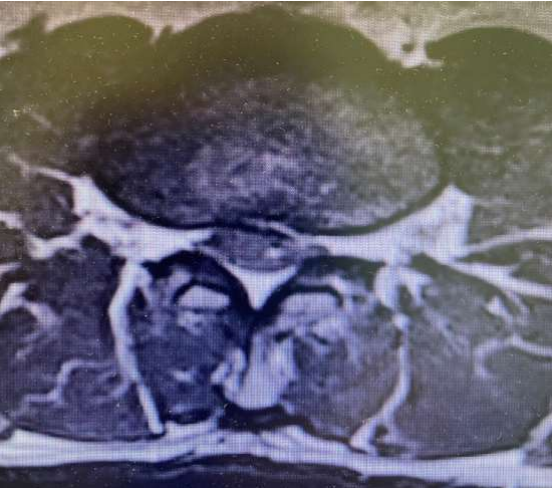

Fig 2: Axial view showing L2/L3 Discopathy with compression

MRI proved to have a large extrude disc fragment at L2-3 level.

with evidence of bilateral compression of L3 foramina.

Figure 2